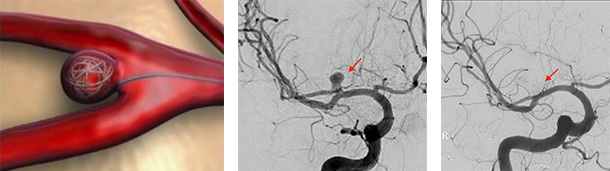

2)血管内治療(コイル塞栓術、フローダイバーター):足の付根の血管からカテーテルを挿入し、そこから動脈瘤のある脳血管までカテーテルを進めていきます。腕の血管からカテーテルを挿入することもあります。動脈瘤の内部に約0.3mm~0.5mm程度の太さのコイル(プラチナ製)を充填していくことで、動脈瘤内へ行く血流を遮断し、破裂を防ぐ方法です。動脈瘤の大きさや形状によっては、フローダイバーターというステントを動脈瘤ができている脳血管に留置することで治療が可能な場合があります。患者さんへの侵襲が少ない治療であり、近年道具の発達に伴って進歩している治療法になります。